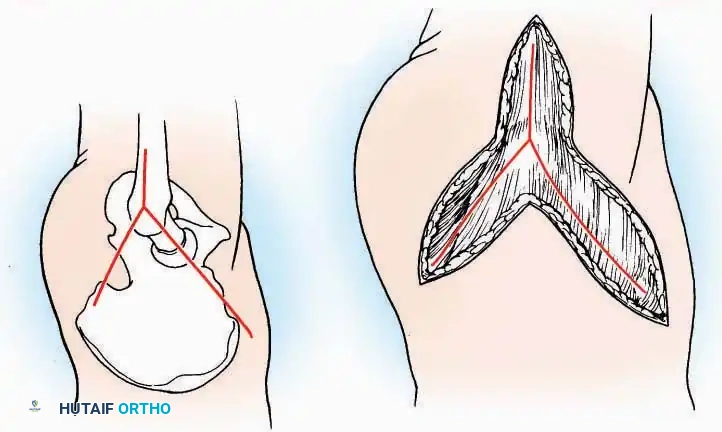

Lateral Approach (Extensile Lateral)

This is the workhorse approach for open reduction and internal fixation (ORIF) of displaced intra-articular calcaneal fractures.

Indications: ORIF of calcaneus fractures, lateral wall exostectomy, subtalar arthrodesis.

Positioning: Lateral decubitus with the operative leg up, or supine with a large bump under the ipsilateral hip to internally rotate the leg.

Surgical Technique:

* Incision: Begin the incision on the lateral margin of the Achilles tendon near its insertion. Extend it distally to a point 4 cm inferior and 2.5 cm anterior to the lateral malleolus. (For trauma, a classic L-shaped extensile incision is often used, dropping straight down anterior to the Achilles, then curving gently toward the base of the 5th metatarsal).

* Superficial Dissection: Divide the superficial and deep fasciae. It is imperative to create a "full-thickness" flap containing skin, subcutaneous fat, and periosteum to prevent flap necrosis.

* Nerve Protection: The sural nerve crosses the proximal and distal limbs of this approach. It must be identified and protected within the anterior flap.

* Deep Dissection: Isolate the peroneal tendons (longus and brevis). Incise and elevate the periosteum below the tendons to expose the lateral wall of the calcaneus.

* Tendon Management: If severe deformity or infection is present, the peroneal tendons may be divided via Z-plasty and repaired at the conclusion of the case, though this is rarely necessary in modern fracture care.